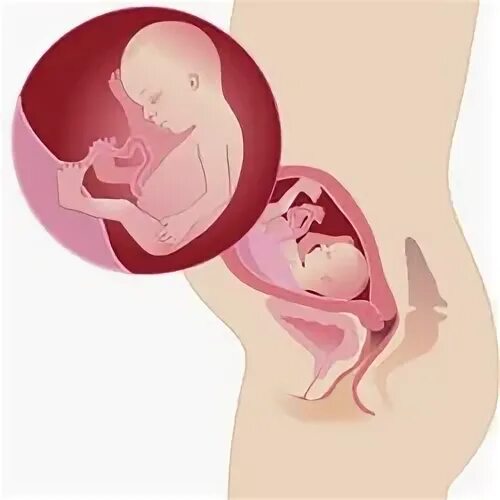

10 неделя беременности ощущения в животе